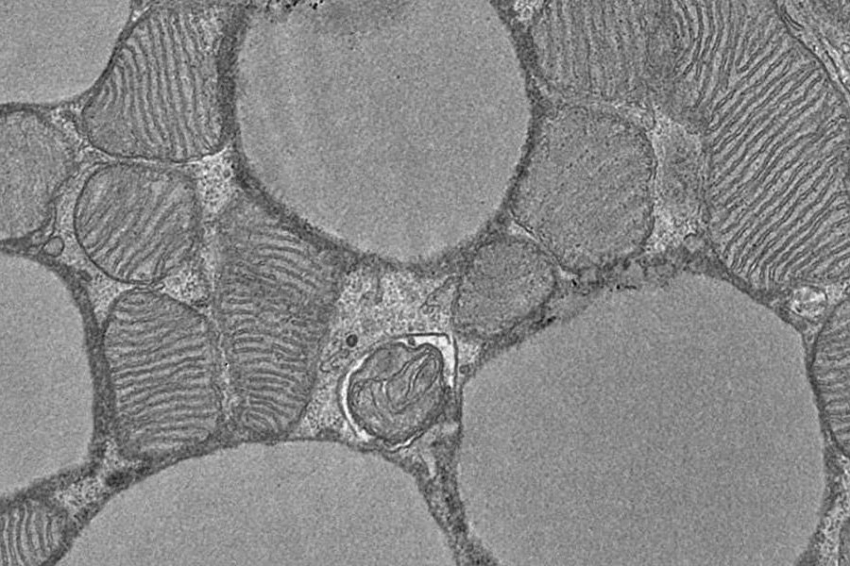

Фото из открытых источников